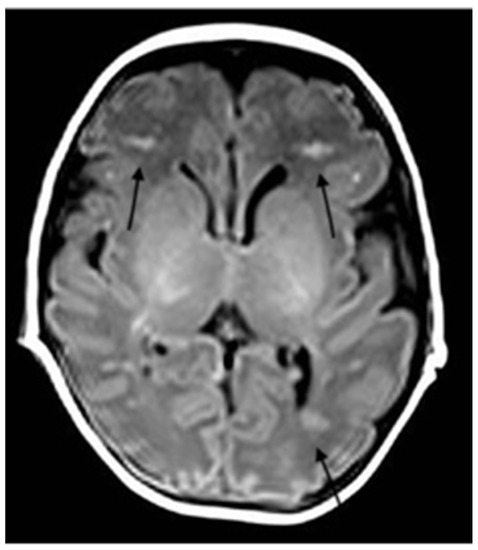

Severe COVID-19 Complicated by Cerebral Venous Thrombosis in a Newborn Successfully Treated with Remdesivir, Glucocorticoids, and Hyperimmune Plasma

2. Case Description